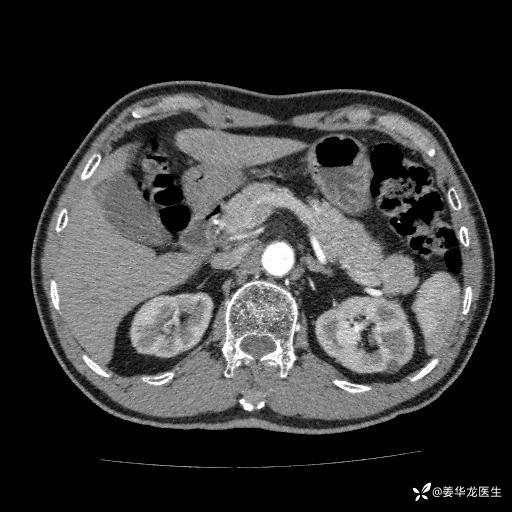

左肾中心型肾门部肿瘤39mm×34mm×36mm,右肾GFR25ml/min,部分切还是全切?

患者75岁老年男性,体重50kg,无高血压、肾病、糖尿病等基础病,检查发现左肾中心型肾门部肿瘤,右肾GFR只有25ml,无肉眼血尿,无镜下血尿。入院验血常规检查均正常,包括肾功能,肌酐102.7umol/L.

二、左肾肿瘤与左肾集合系、左肾动静脉关系密切,左肾部分切除术可行吗?成功率有多大?成功部分切后,肾功能还有多少?